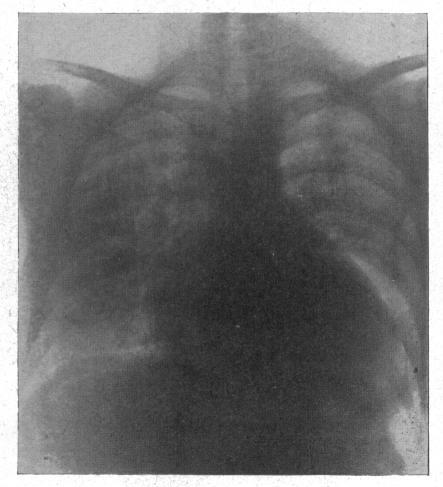

The radiology of acute pulmonary oedema.

Br Heart J. 1951 Oct;13(4):503-18. doi: 10.1136/hrt.13.4.503.